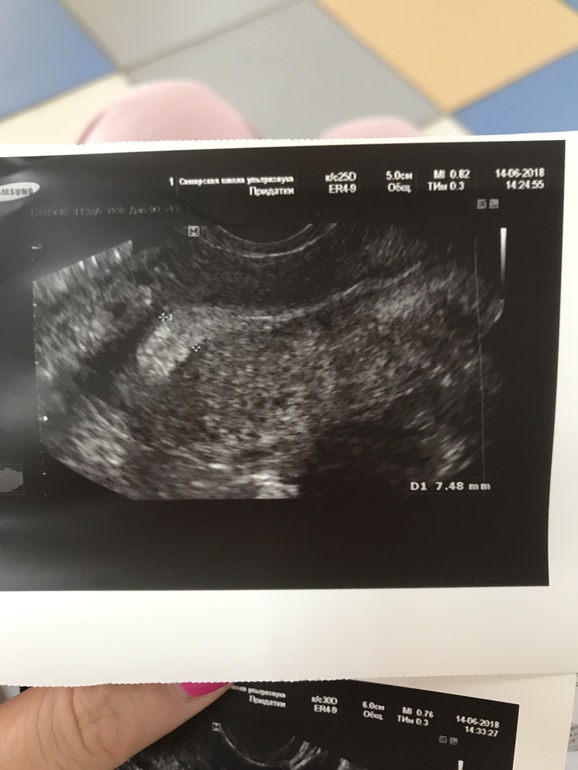

И вот сейчас 22 -й день цикла , была в отъезде , не было возможности делать УЗИ , делала тесты на овуляцию с 9 по 14 дц , но так и не дождалась положительного результата ( брала клеоблю - так и не дождалась улыбку )) не помню точно с какого дня , но неделю точно уже ( т.е с 15 дц ) начались боли в боках и слева и справа , но не прям где яичники , а выше .... эти боли мне прям дискомфорт доставляют ... усиливаются почему-то вечером тли прям когда спать ложусь 🤔 сегодня решила заехать на УЗИ глянуть что там ) и посмотреть была или не была овуляция .... и вот вышла и думаю , что лучше бы не заезжала ... одни неясности .. узитска ни на что не дала гарантий , все у неё под вопросом , и наставила кучу диагнозов 🤦♀️ Вышла вот вся в сметении и расстройствах , может кто разбирается и по фото может понять что и как ?